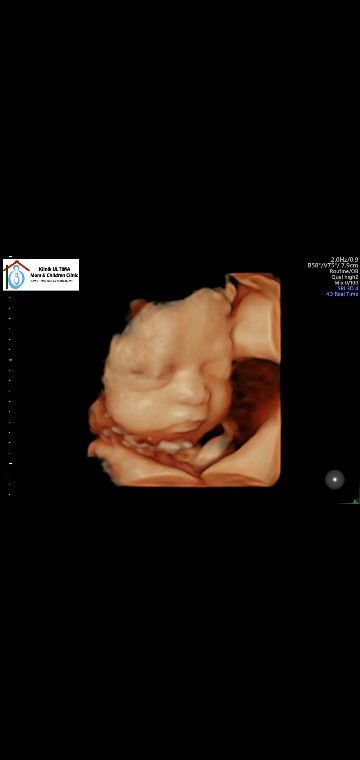

Bunda, adakah disini yang HPL hari ini? Sharing yuk, Bunda. kemarin aku USG di dokter SpOG(KFM) atau dokter spesialis kandungan Konsultan Feto Maternal. Calon baby-ku masih di posisi posterior atau wajah baby menghadap kedepan / ke perut ibu. Sedangkan posisi terbaik bayi yang akan lahir adalah posisi anterior atau wajah bayi menghadap ke punggung ibu. Saya sudah mencoba berbagai cara biar calon baby mau muter badan ke posisi ideal/anterior, dokter ngasih saran buat rajin jalan pagi, itu pun udh saya jalani sampe kaki gemeteran. Belum bisa HB sama suami soalnya suami sedang pengobatan sakit kanker ginjal. Nungging juga udah sering sampe nafas agak sesek. Ngajak bicara baby juga udah, sambil minta biar baby mau lepasin lilitan dilehernya. Adakah diantara bunda2 yang pernah melahirkan baby dengan posisi posterior? Melahirkan secara normal atau Caesar? Benarkah kemungkinan bisa normal tapi dengan proses persalinan yang lama dan lebih menyakitkan dibanding melahirkan baby posisi anterior? Sedikit curhat ya bun. Disaat hamil tua saya harus menerima kenyataan kalo suami di vonis kanker ginjal, harus LDRan dan nggak bisa nemenin suami berobat karena sudah mendekati HPL. Apalagi calon baby-ku belum diposisi mapan. Oh iya. Bunda2 yang baik, saya mohon do'anya ya, supaya saya dan suami kuat dan tabah menjalani semua ini, semoga calon baby kami cepet muter badan dan segera lahir sehat tanpa kurang suatu apapun. Aamiin. Terimakasih buat bunda2 di aplikasi TAP yang sudah berbaik hati meluangkan waktunya untuk mendo'akan saya, suami, dan calon baby. Semoga Allah SWT membalas kebaikan bunda2 dengan pahala yg berlimpah. Maaf agak curhat ya bun. Sesek di dada kalo dipikul sendirian?